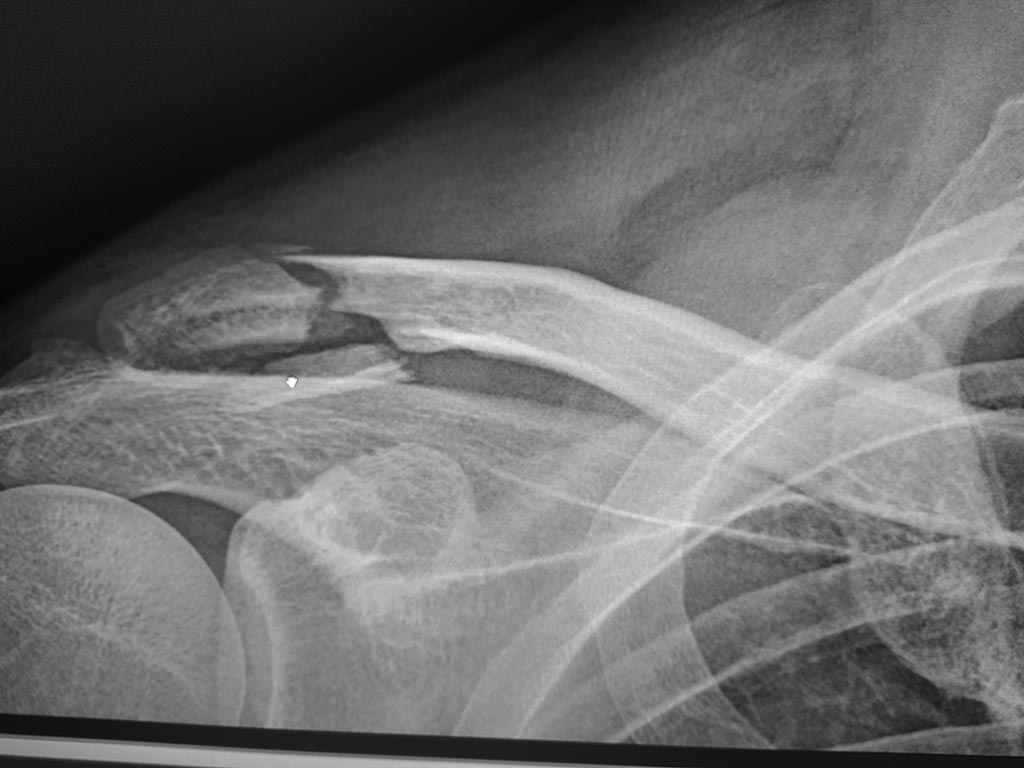

[Ortho] Перелом ключицы

Мужчина, 47 лет. Оперировать или само срастётся. Нужно мнение сообщества.